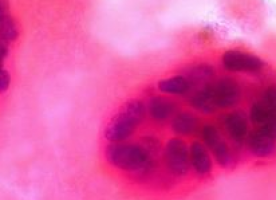

Tamoxifen inhibits the growth of hormone-sensitive breast cancer cells by preventing the hormone oestrogen from binding to its receptor in the tumour cells.